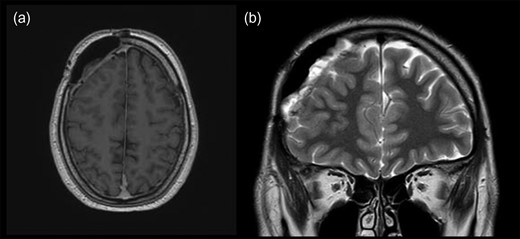

A 34-year-old male patient was presented with a 2-month history of intermittent headaches in the right frontal region. No other significant neurological deficits were found. Initial magnetic resonance imaging (MRI) revealed mass in the right frontal part of the skull (Fig. 1). The mass was attached to dura mater and it was mildly compressing the middle frontal gyrus beneath. Also, signs of intraosseal propagation were present. Patient underwent right side frontal craniectomy. Bone attached to the tumor was extracted. Duroplasty and cranioplasty were performed. Surgery went without complications. Postoperative computerized tomography (CT) was satisfying. Tissue samples from multiple sites of tumor connected to dura with surrounding bone were taken intraoperatively and underwent histopathological analysis. Tumor consists of large cells with pleomorphic nuclei and prominent nucleoli, with pathological mitotic figures. Tumorous tissue shows immunohistological reactivity for CD45 LCA, CD20, CD79a, CD10, BCL6 and PAX5. They were partly positive for BCL2 and CD30 and negative for CD3 and CD21. C-myc shows positivity in 36% of tumor cells. Proliferation index Ki67 is diffusely 75% (Fig. 2). According to WHO classification it corresponds to diffuse large B-cell lymphoma. Afterwards, extended diagnostics were performed. Bone marrow biopsy showed an abnormality in the percentage of non-segmented neutrophils of 17%. Other results showed medium–high erythropoiesis with normal cell ratios but without findings of malignant alteration or infiltration. A cylindrical sample showed no morphological nor immunohistochemical (CD20, PAX5, Ki67 and CD3) evidence of malignant infiltration. Lumbar puncture was also performed and cerebrospinal fluid (CSF) samples showed no positivity to malignant cells. Afterwards, full body CT was performed, followed by ultrasound including thyroid and salivary glands. Also, MRI of brain and spinal cord was done. All conducted imaging methods revealed normal anatomical and structural features without traces of lymph node enlargement or flee fluid throughout the body. A hematologist was consulted and methotrexate or R-CHOP therapy was recommended.

Initial brain MRI showing extra-axial mass in the right frontal part of anterior cranial fossa in (a) transverse and (b) coronal plain.